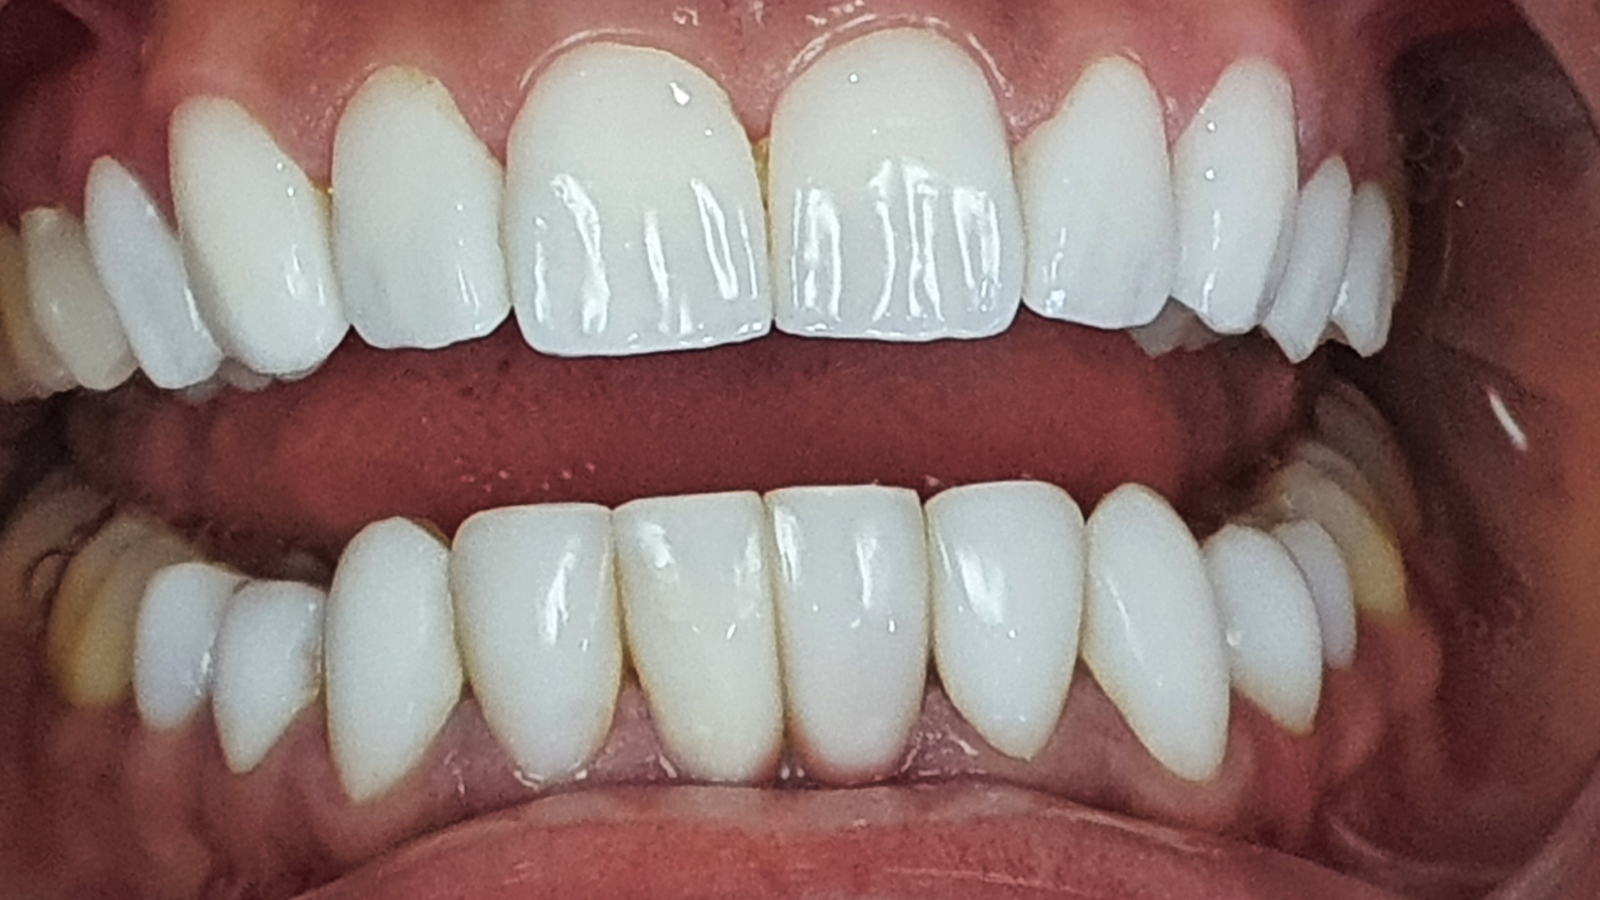

Restaurations des incisives : un sourire plus naturel

Jeune patiente qui présentait des restaurations sur ses incisives.

L’objectif : un sourire naturel avec les ingrédients qu’il faut — translucidité, relief et forme.

Les images montrent une amélioration de l’harmonie du secteur antérieur, avec une meilleure homogénéité (teinte/texture) et des contours plus réguliers pour un rendu plus naturel.

Images :